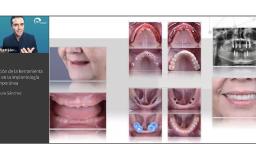

Esta presentación pretende explicar, a través de datos de la literatura, como obtener resultados estéticos con cirugía sin colgajo (flapless). Describe las ventajas del abordaje sin elevación de colgajo en sitios con mucosa ceratinizada y suficiente volumen óseo, así como las limitaciones de la técnica.

Se discuten aspectos fundamentales de los tejidos duros y blandos para obtener resultados predecibles en los casos de instalación inmediata de implantes en alvéolos post extracción (Tipo 1), centrándose en los riesgos y la necesidad de cuidadoso diagnóstico y plan de tratamiento.

identificar las indicaciones y ventajas de la cirugía sin colgajo

evaluar los factores de riesgo estético con implantes inmediatos

describir y discutir las claves para éxito estético